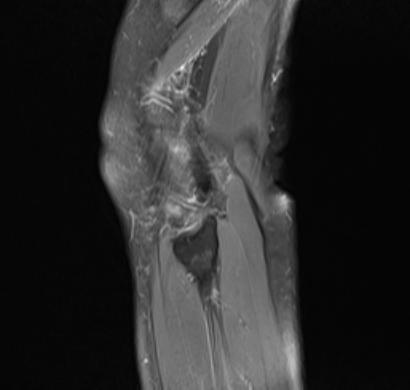

MRI6674:膝关节后囊性病灶。

F,55Y,膝部病痛月余。我考虑骨关节炎,骨髓再生,内侧半月板后撕裂,现一问题请大家指导,关节后部是滑膜骨软骨瘤病?

矢状位第14层